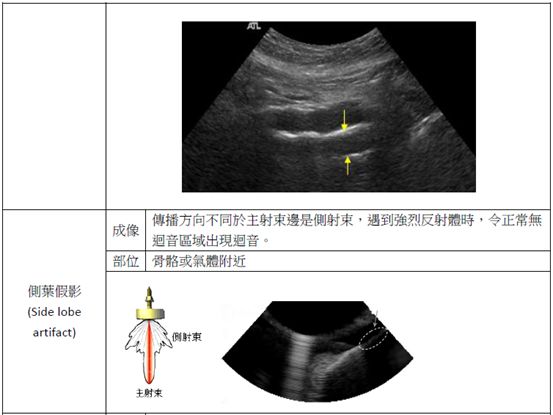

58.下圖之超音波影像中,編號45的區域屬於下列何種假影?

(A)acoustic shadow

(B)distal acoustic enhancement

(C)comet tail artifact

(D)section-thickness artifact